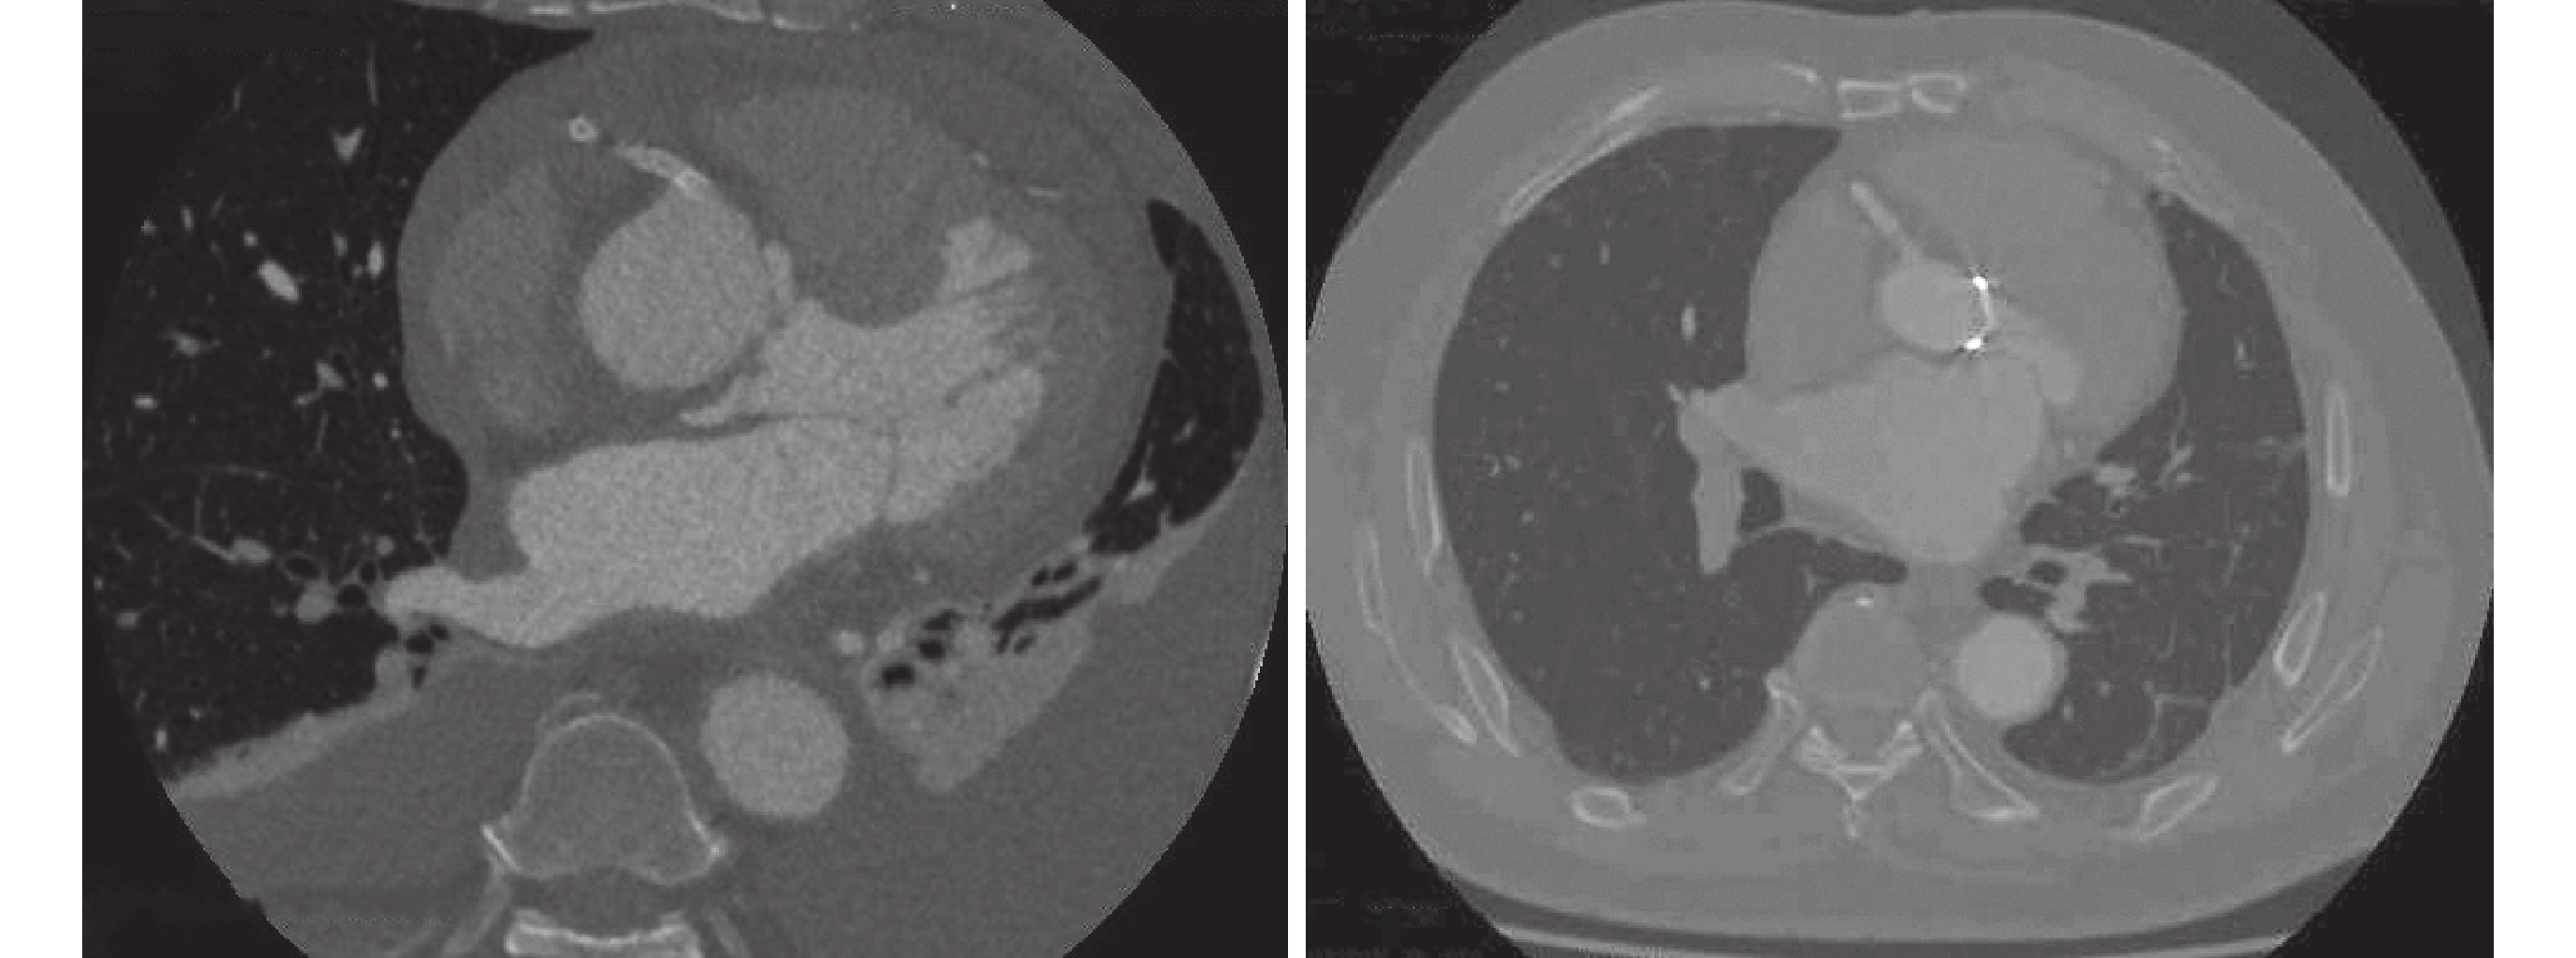

導管相關的醫源性主動脈夾層發生率不高,國外報告發生率在0.039%[6],我中心報道的一組病例發生率為0.03%[7],與國外文獻基本一致。針對冠脈介入操作所造成的主動脈病變,不同中心處理的方式有所不同。Dunning等[8]總結了9例冠脈介入相關性主動脈夾層,將其簡化分為3型。I型是夾層僅局限于主動脈竇;Ⅱ型是累及升主動脈但不超過4 cm;Ⅲ型也是最嚴重的一種類型,累及范圍超過4 cm。針對不同類型,作者提出了不同的治療方案。Ⅰ型與Ⅱ型保守治療效果理想,但Ⅲ型保守治療效果不佳。本組6例醫源性主動脈夾層均屬于Ⅲ型;見圖1。術前均應用了2種血小板抑制劑,經手術治療后均順利康復出院。PCI相關醫源性主動脈夾層的患者雖然術前應用血小板抑制劑再加上急性心肌缺血的風險,如果進行體外循環手術可能帶來災難性的后果;但是對于Ⅲ型的患者,手術治療仍然是有必要的。結合我中心的經驗,我們建議局限的主動脈夾層或主動脈壁內血腫先采取保守治療的措施,如果觀察期間出現明顯胸痛等癥狀或灌注不良等情況應該及時手術治療;對于廣泛受累的Stanford A型主動脈夾層要積極手術治療。